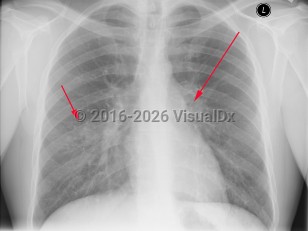

Symptoms of pulmonary TB are nonspecific and include anorexia, fatigue, anemia, weight loss, fevers, and night sweats. Cough is usually productive, and hemoptysis may occur. Pleural involvement may lead to chest pain and dyspnea. Physical examination findings include rales and signs of consolidation. Auscultation over cavities may reveal amphoric breath sounds (like the sound made by blowing across the mouth of a jar). Signs of pleural effusion may also be found. Pericarditis and pericardial effusion can occur.

The clinical manifestations of TB in HIV-infected patients correlate with the degree of immunosuppression. In general, patients with early HIV present with similar features to those without HIV. Patients with advanced HIV and TB may present with unusual manifestations such as the involvement of middle and lower lobes, negative purified protein derivative (PPD) testing, less cavitary disease, and more frequent extrapulmonary disease, especially lymphadenitis and pleurisy. In these patients, TB can also present with acute respiratory failure and acute respiratory distress syndrome. In older adults, newly acquired pulmonary TB may present with nonresolving pneumonitis of the middle and lower lobes. In countries with a high burden of HIV infection and TB, patients may present with sepsis and organ dysfunction.